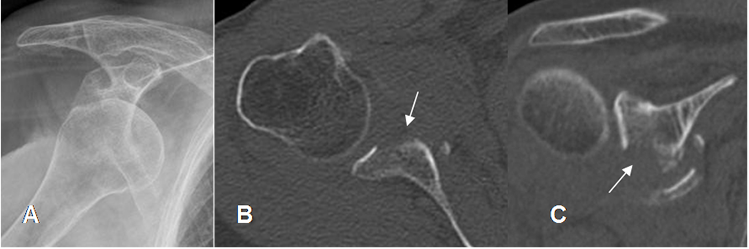

Fig 65. Lesión de Bankart óseo.

A: Rx AP. Signos de luxación anterior.

B: TAC axial y C: TAC reconstrucción coronal. Fractura del reborde antero-inferior de la glenoides, con fragmentos sueltos, por bankart óseo.